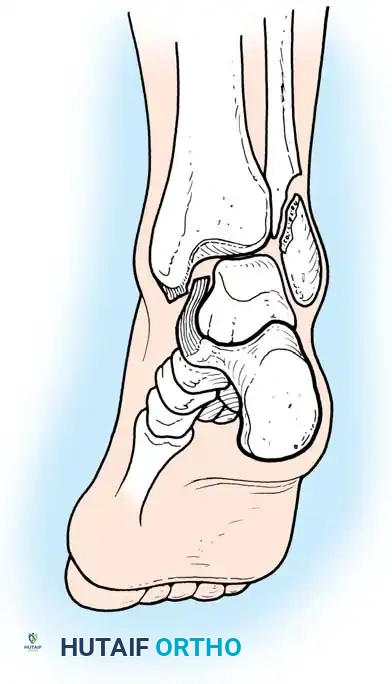

Injuries around the ankle joint cause destruction of not only the bony architecture but also, critically, the ligamentous and soft-tissue components. The ankle is a highly congruent, weight-bearing hinge joint. With fractures of the ankle, only slight variation from normal anatomy is compatible with good long-term joint function. Classic biomechanical studies have demonstrated that even a 1-mm lateral shift of the talus reduces the tibiotalar contact area by 42%, leading to exponentially increased peak contact stresses and rapid post-traumatic arthrosis.

Bimalleolar Fractures

Bimalleolar ankle fractures disrupt both the medial and lateral stabilizing structures of the ankle joint. Displacement drastically reduces the tibiotalar contact area and alters joint kinematics. While closed reduction can often be accomplished acutely, it is rarely maintained as swelling subsides.

Surgical Sequence for Bimalleolar Fixation

- Lateral Side First: The fibula is typically addressed first to restore the length and rotation of the lateral column. This often indirectly reduces the talus and simplifies the medial reduction.

- Medial Side Second: Once the lateral mortise is established, the medial malleolus is directly reduced and fixed.

- Syndesmotic Evaluation: After bimalleolar fixation, the syndesmosis must be tested using the "Cotton test" (lateral traction on the fibula using a bone hook). If widening occurs, syndesmotic screws or flexible suture-button constructs are required.